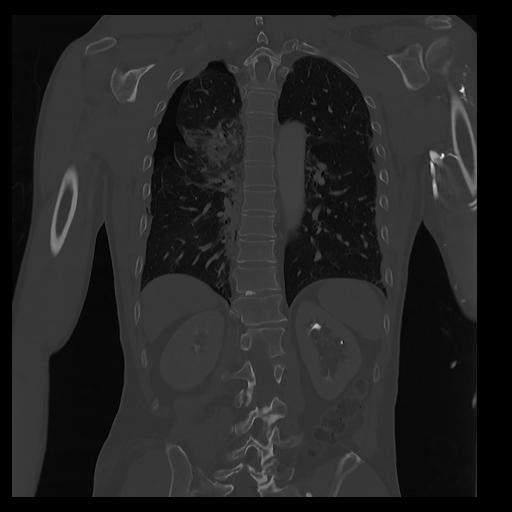

32 PULMON,CE,Coronal,3.000,PULMON,Coronal,